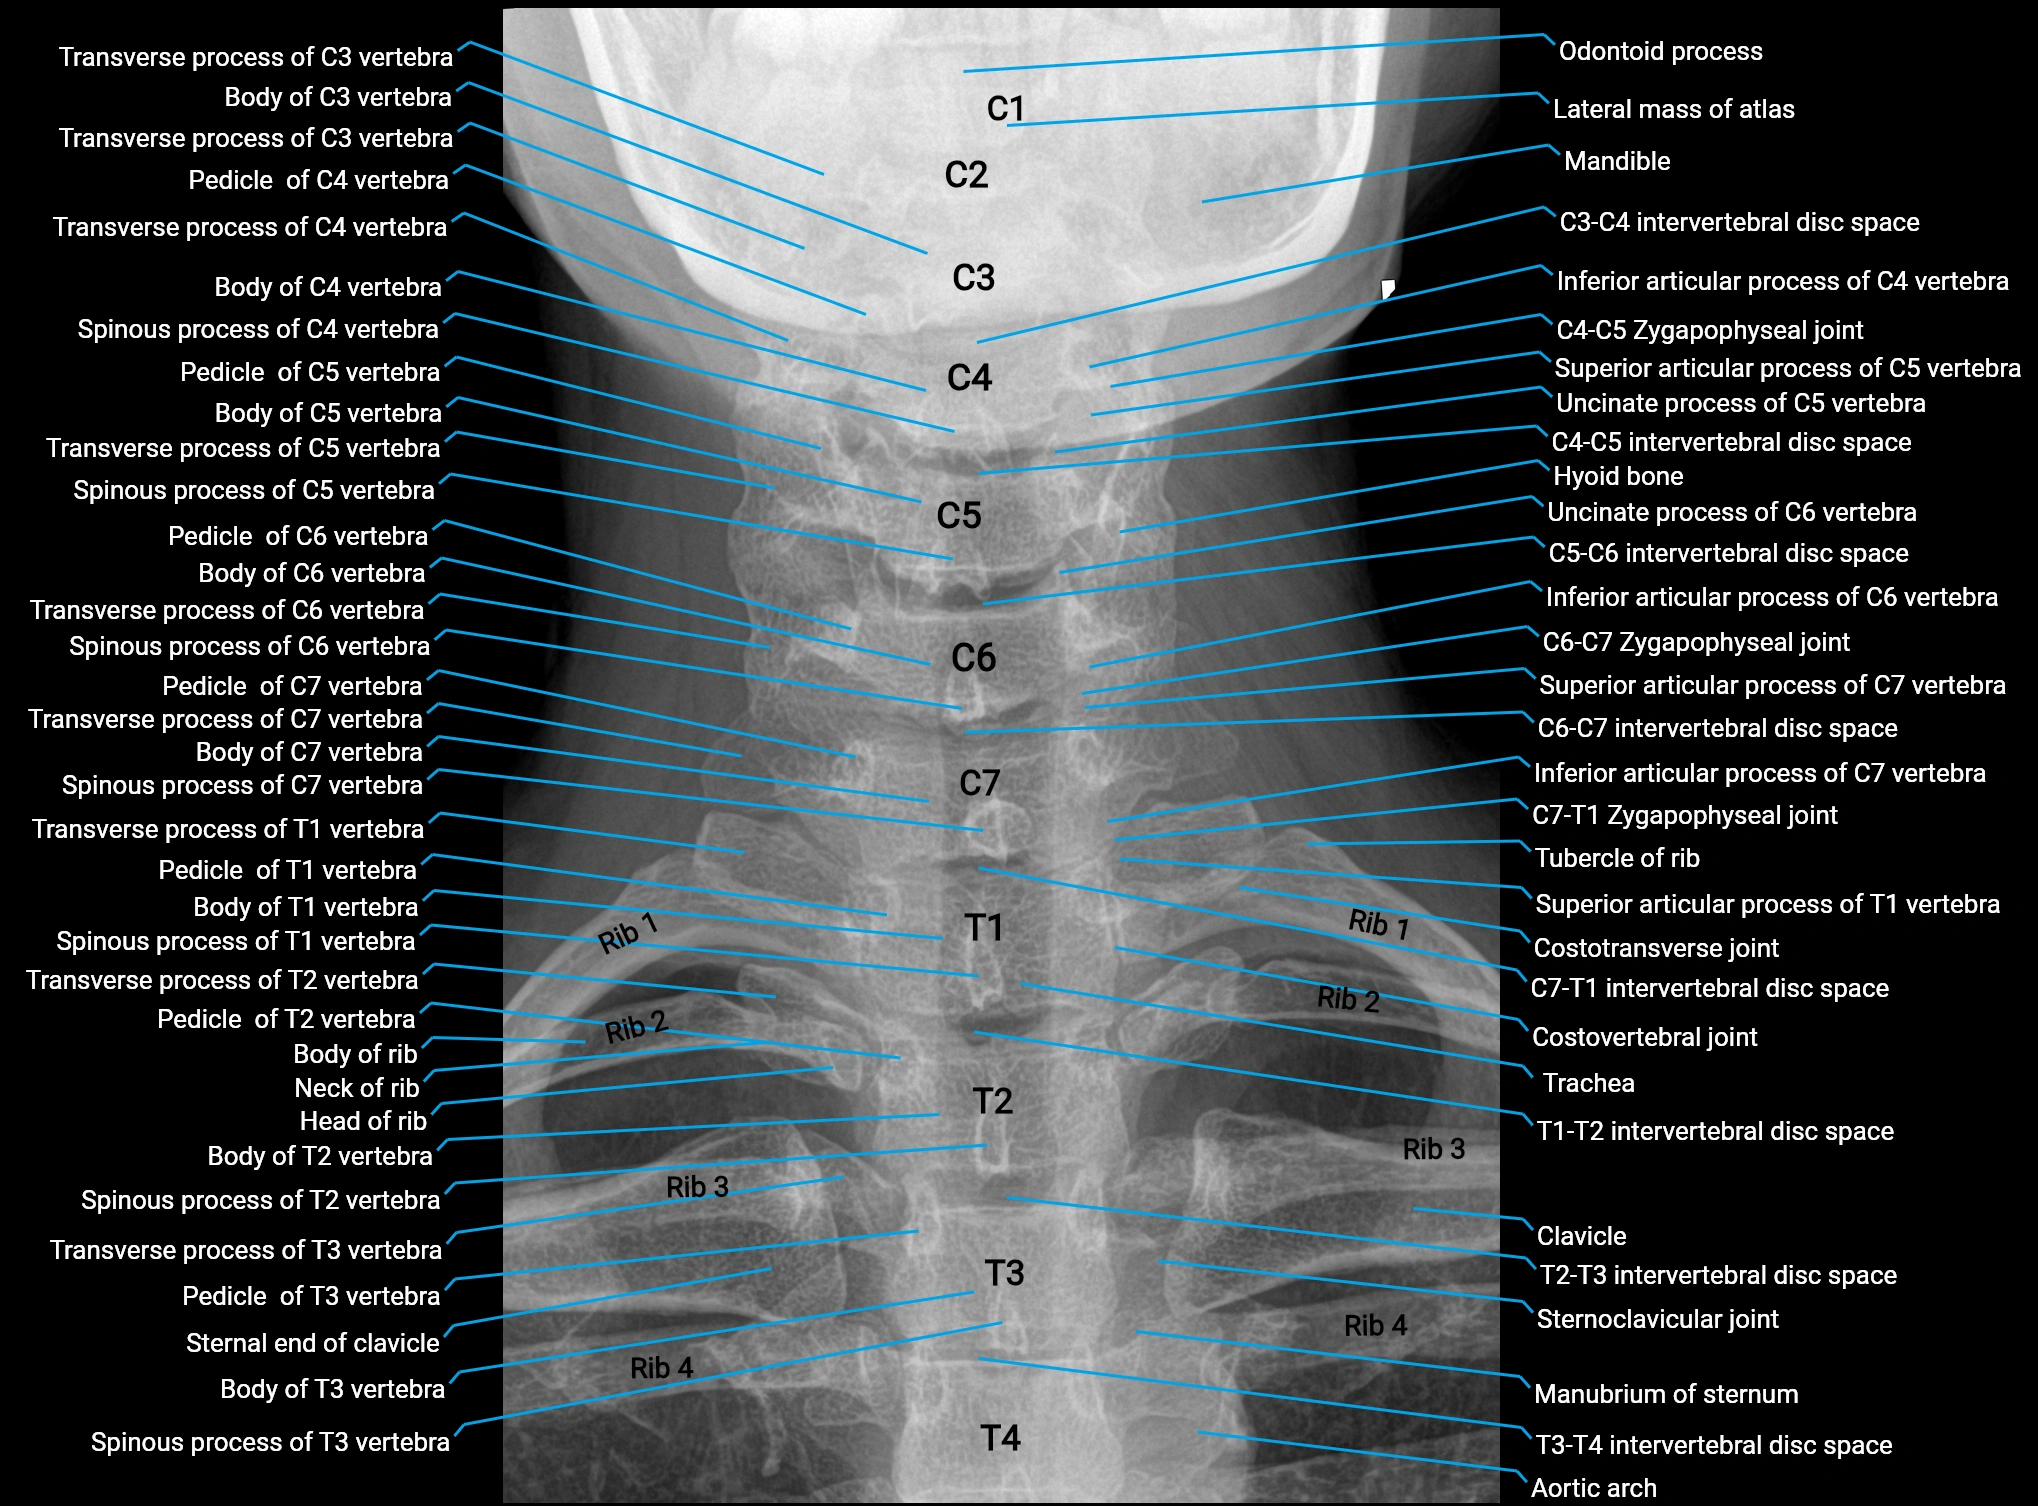

X-ray appearance

Spine radiographs (AP / lateral views):

• Annular epiphysis: Thin, linear bony rim along vertebral endplate margins

• Appearance: Smooth, well-corticated ring

• Age dependence: More conspicuous in children and adolescents

• Fusion: Disappears after complete fusion with vertebral body